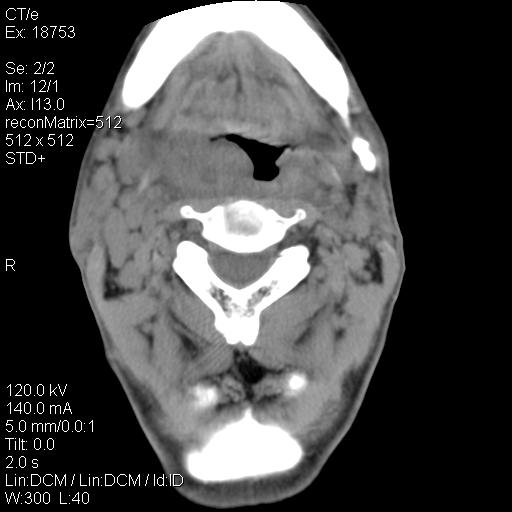

标题: CT21693:男 58岁 右侧咽部疼她2天余 PE:右侧扁桃体肿大 压痛 [打印本页]

标题: CT21693:男 58岁 右侧咽部疼她2天余 PE:右侧扁桃体肿大 压痛

1 弥漫性肿胀,与周围组织分界清晰,发病急,有明显症状,考虑急性炎症【wbc]

弥漫性肿胀,与周围组织分界不清,发病急,有明显症状,考虑:感染性病变!

右化脓性扁桃体炎症伴咽后壁脓肿形成.